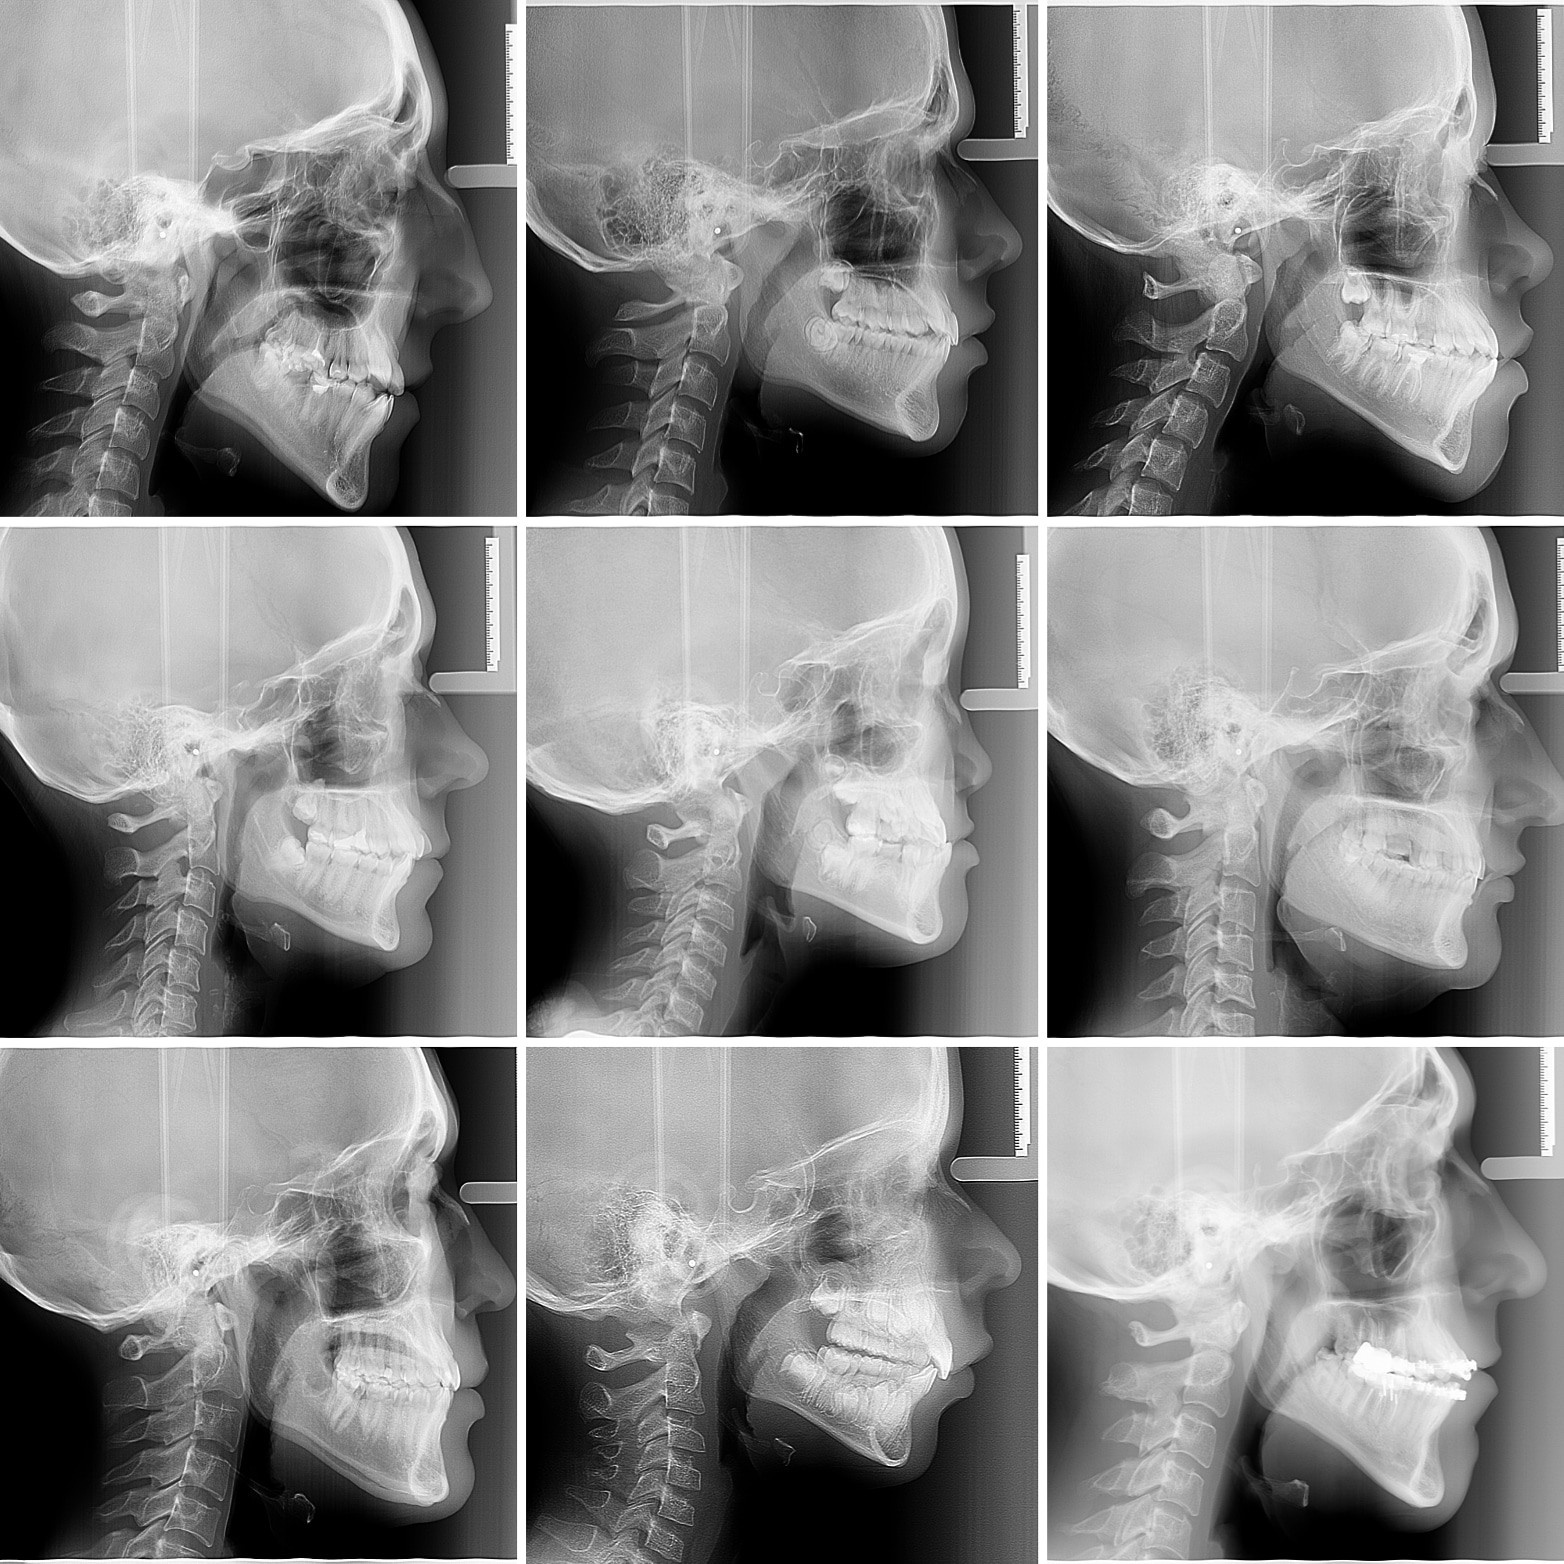

Иван Тимофеевич 😎проходит лечение с использованием аппарата Марко Роса и ЛИЦЕВОЙ МАСКИ. Мама большая молодец, она обратила внимание на формирующийся неправильный прикус сына и вовремя обратилась за помощью.

Лицевая маска - это внешний аппарат, который выступает в качестве опоры для выдвижения (стимуляции роста) верхней челюсти. Подробнее о лицевой маске в следующих постах.

Современная ортодонтия - это не просто ровные зубы... Прикус исправляем "с запасом" с ориентацией на дальнейший рост нижней челюсти. Лечение продолжается...

МЕЗИАЛЬНЫЙ ПРИКУС - такой вид прикуса, когда нижняя челюсть находится впереди верхней (в норме верхняя и нижняя челюсти должны быть примерно на одном уровне, а верхние зубы должны быть чуть впереди нижних).

❓ От чего бывает такой прикус?

▶️1. Недоразвитие верхней челюсти в передне-заднем направлении 2. Слишком сильное развитие нижней челюсти в передне-заднем направлении 3. Сочетание предыдущих признаков

❓Как работает лицевая маска?

▶️Резиновые тяги, которые цепляются одним концом к крючкам аппарата Марко Роса, а другим к балке лицевой маски, "вытягивают" верхнюю челюсть вперёд, таким образом стимулируя её рост и развитие. Лицевая маска выступает в качестве опоры (лобный упор и подбородочный упор).

❓Как крепится лицевая маска?

▶️Маска держится на лице за счёт резиновых

❓Какой режим ношения лицевой маски?

▶️Чем больше, тем лучше. В идеале постоянно. Для появления эффекта от лечения необходимо ношение минимум 12-16 часов в сутки, то есть всю ночь и несколько часов днем.

❓Как долго её носить? ▶️При соблюдении режима 6-12 месяцев, но чем дольше, тем лучше.

❓В каком возрасте используется?

▶️В 5-8 лет (лицевая маска+Марко Роса). В случае мезиального прикуса чем раньше, тем лучше. Если ребёнку установлен такой диагноз, то начинать нужно уже в молочном прикусе, то есть в 5 лет.